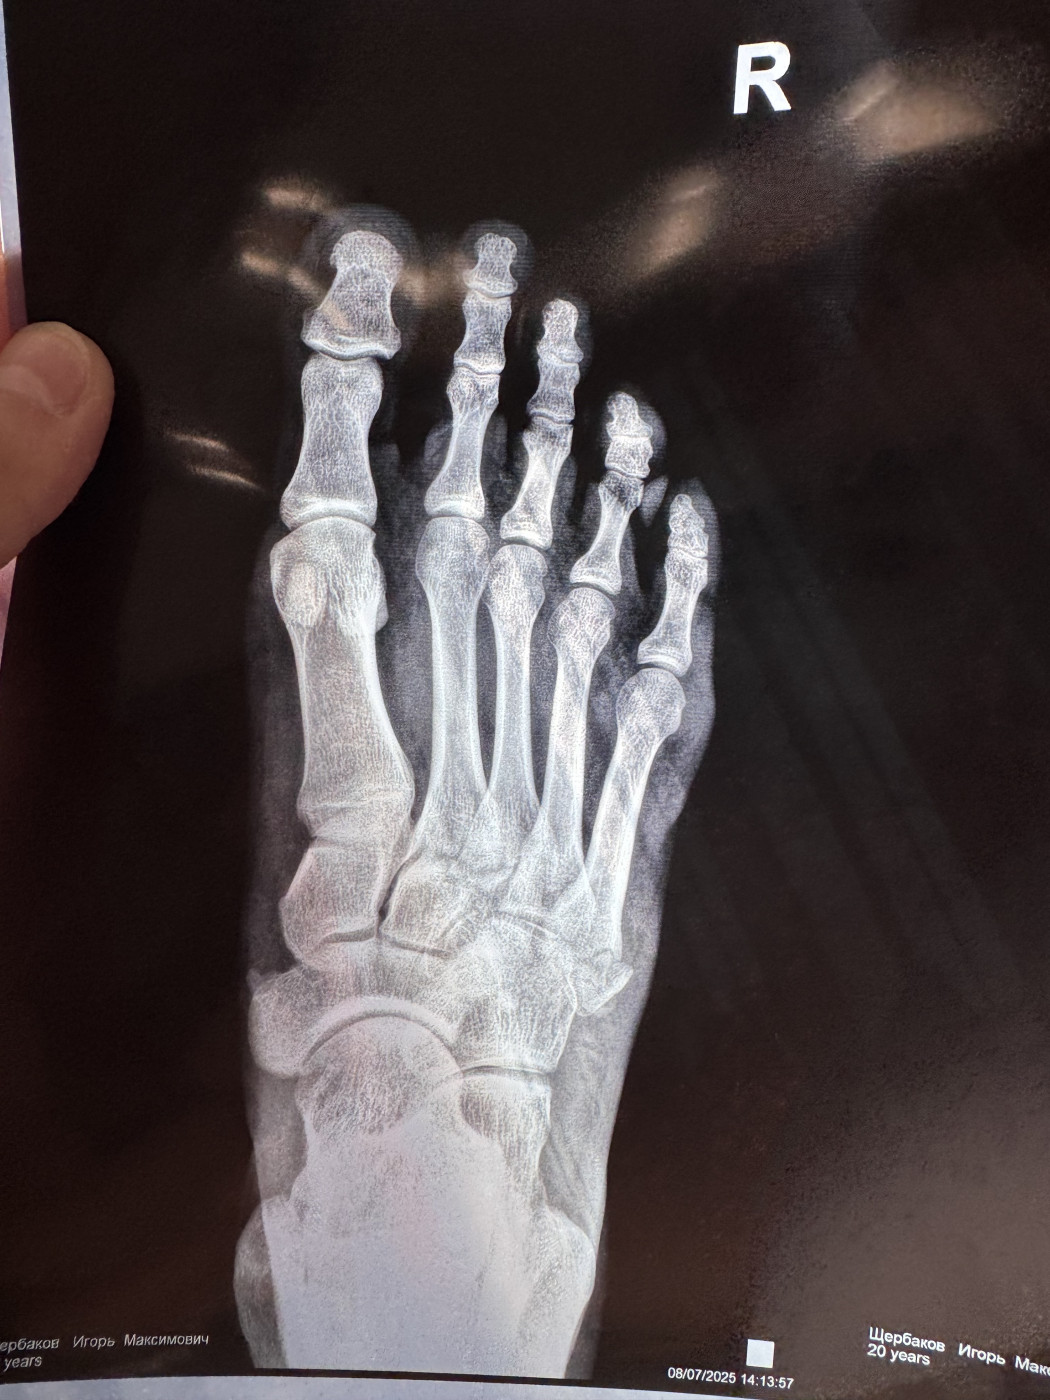

Перелом основания 5-й плюсневой кости правой стопы   1 ответ

Здравствуйте, получил перелом основание 5-й плюсневой кости правой стопы, отек уже спал. Появились синяки у основания пальцев и на самих пальцах, синяки проходят, но к сожалению не сделал гипс сразу, только снимок рентген, стараюсь минимальную нагрузку давать, хожу опираясь на другую ногу. Боли практически нет, иногда появляется наплывом, но проходит…

Расшифруйте снимок   2 ответа

Мой папа упал. Делали снимки и врач сказал, что он сломал, какую кость. Я не знаю, потому что его возил племянник. Подскажите пожалуйста что он сломал. Снимки прикладываю!